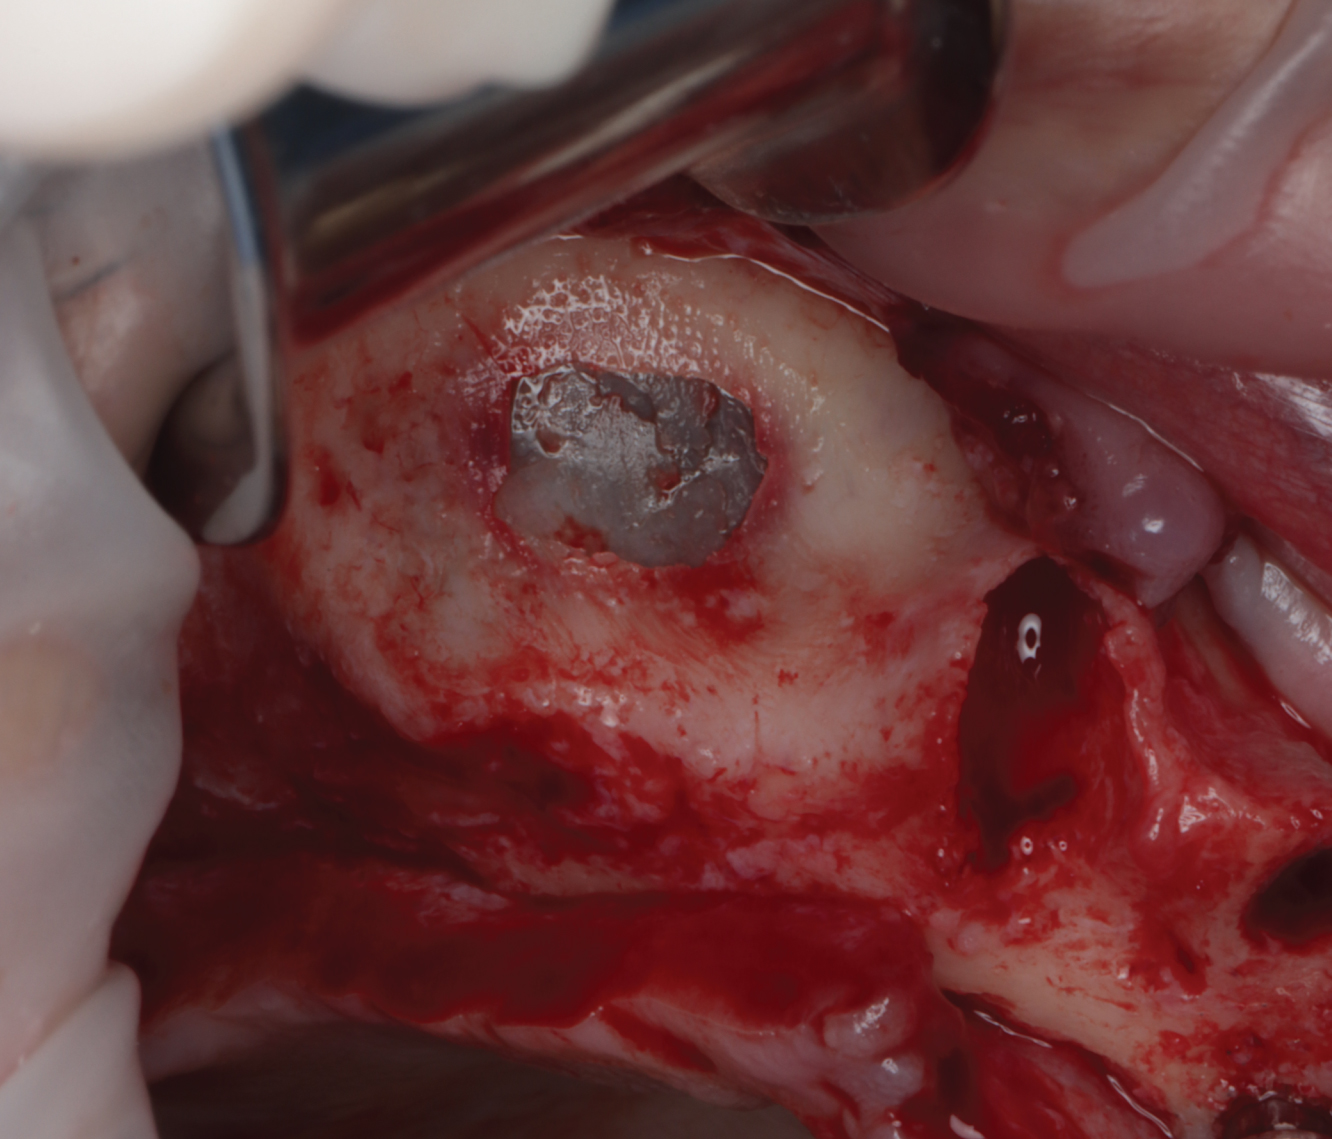

Director’s Clinical Cases

Director’s Clinical Cases